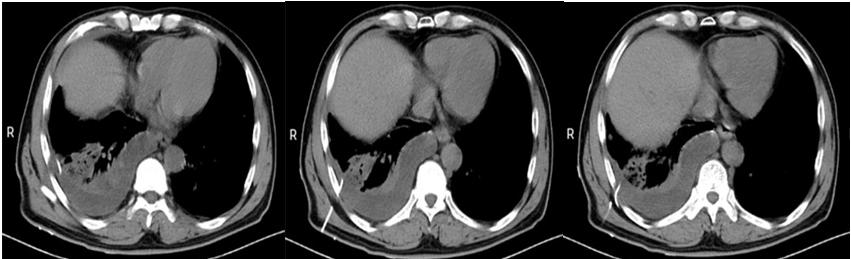

(三)胸部CT:双肺感染性病变,双肺多发高密度片状影(图一所示)。

入院时胸部CT(图一)